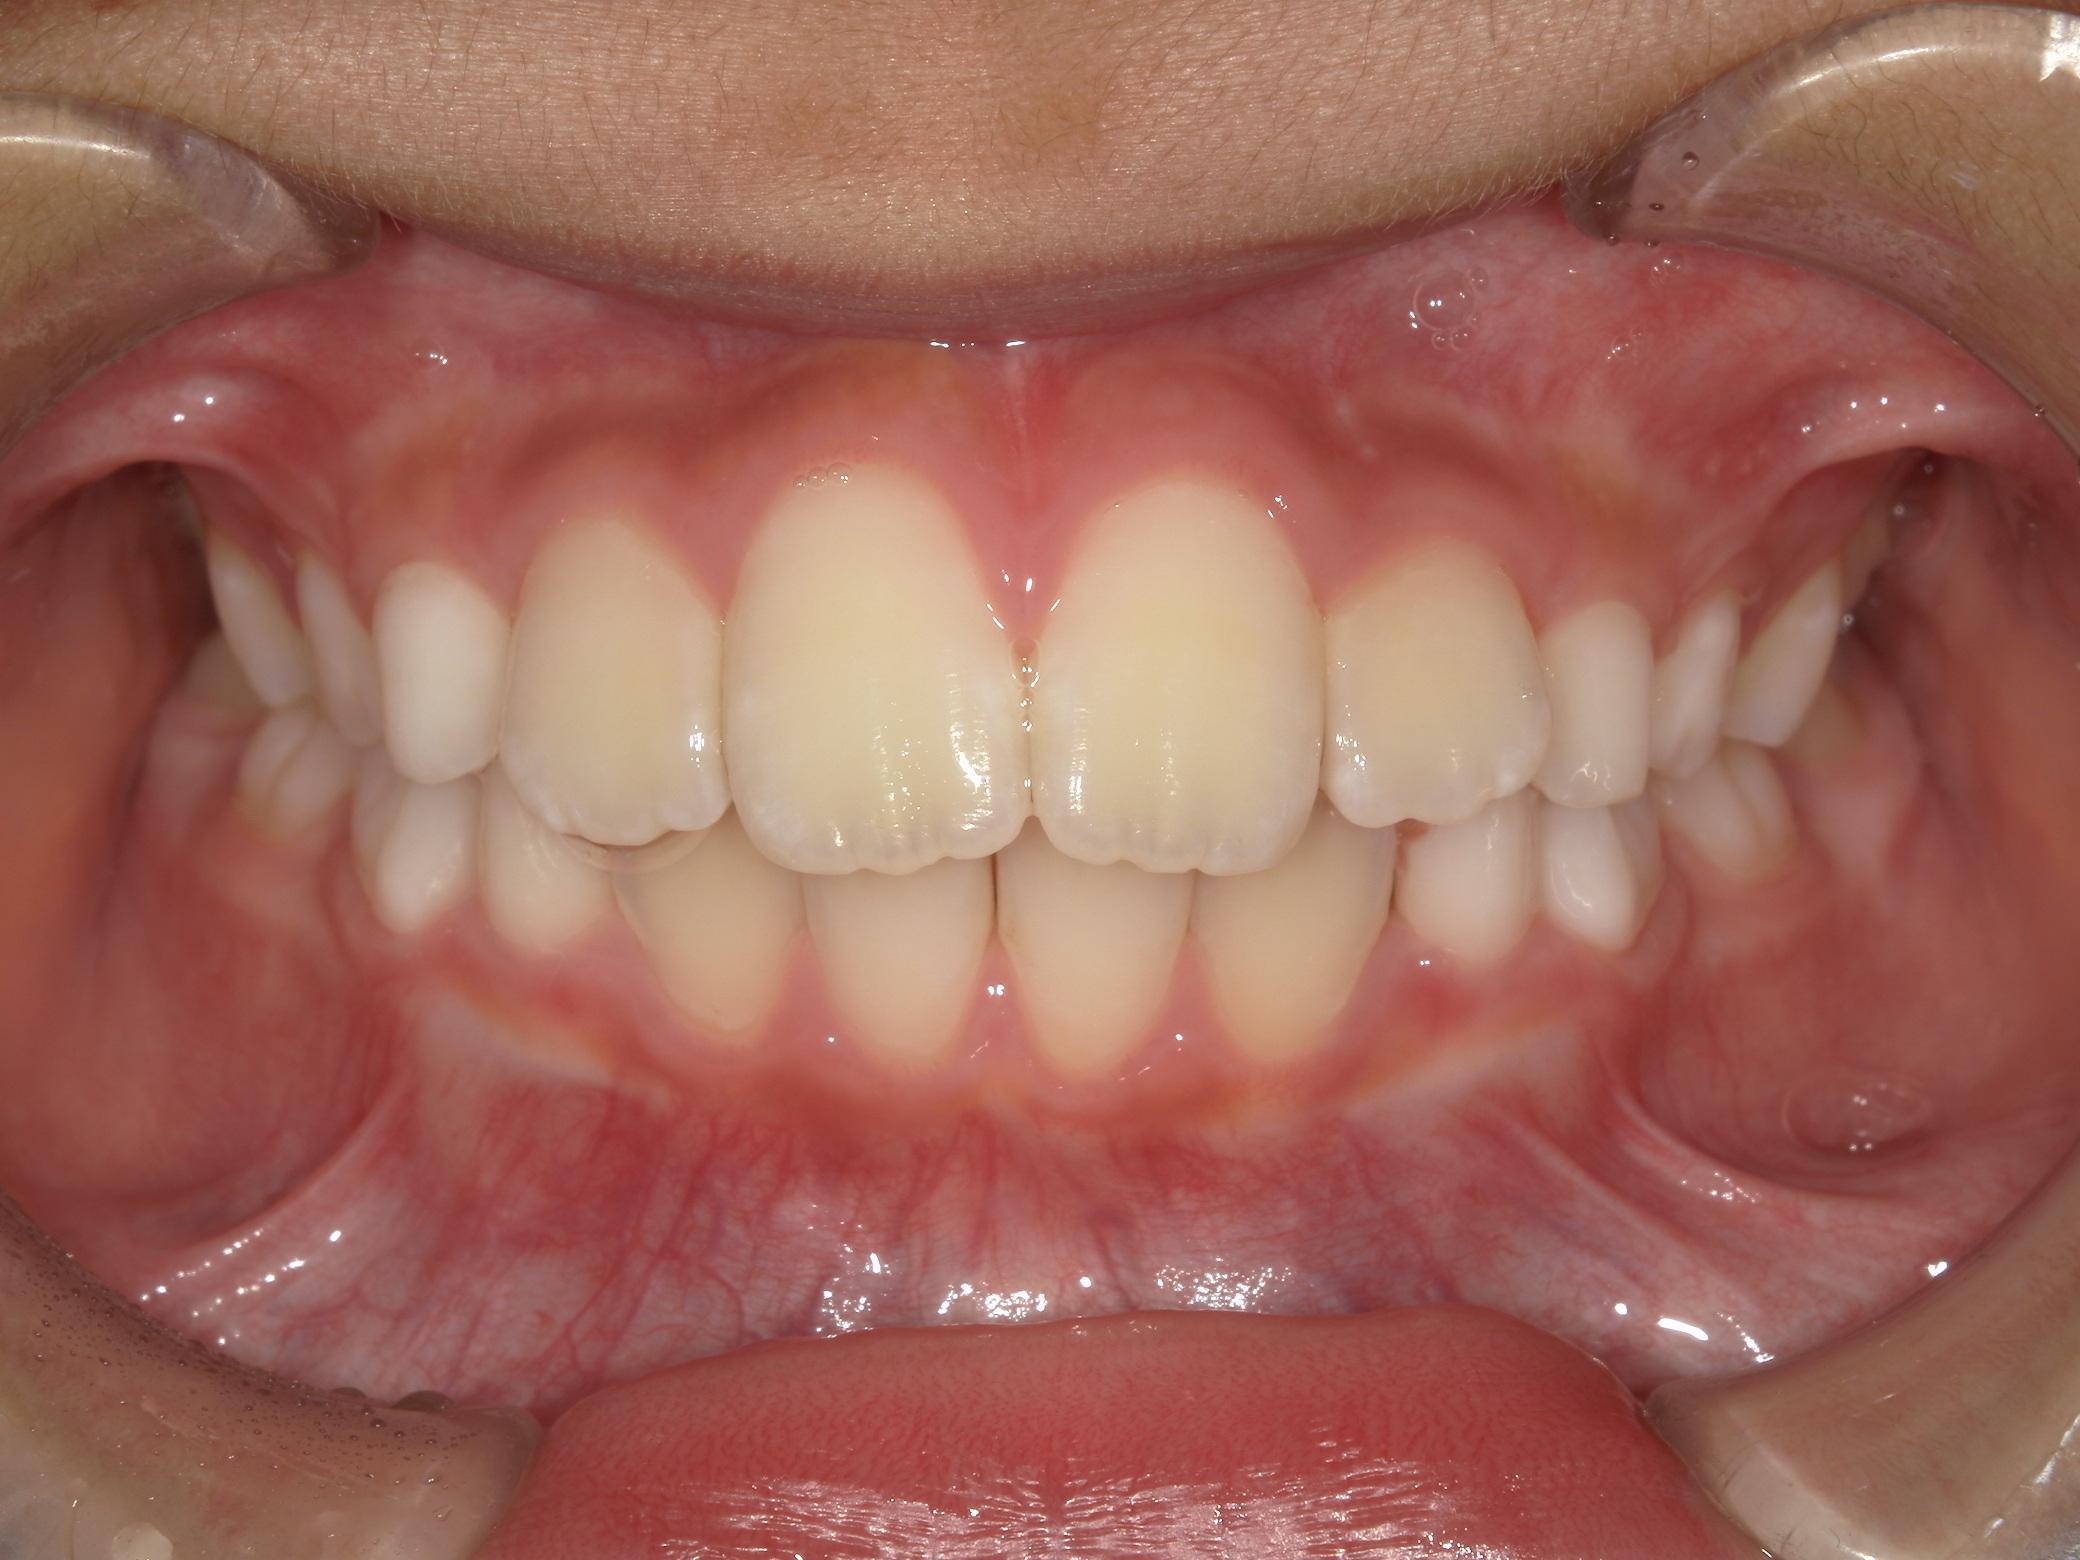

バイオネーターの症例

主訴 | 上の前歯が気になる |

---|---|

治療内容 | バイオネーター |

治療期間 | 1年 |

治療費用 | 330,000円(税込) |